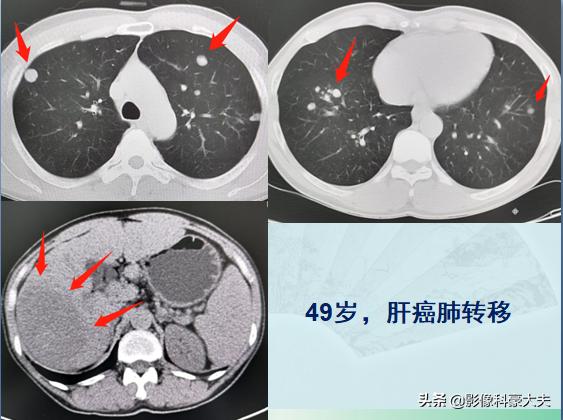

这是一位49岁的农村男病人,在田里干农活时突然觉得右上腹痛,放射到右边肩膀,越来越疼,赶忙撂下农具来医院挂了急诊。CT结果很残酷,癌症晚期:

他的双侧肺叶长了十余个类圆形结节,最大的1.2cm,这种形态首先要想到转移瘤。医生顺着片子往下找,在他的右上腹肝脏位置发现了原发肿瘤(左下图片箭头所示),已经超过9厘米。这是一位肝癌肺转移的病人,晚期了,因为突发上腹痛发现半天,之前没有明显症状。